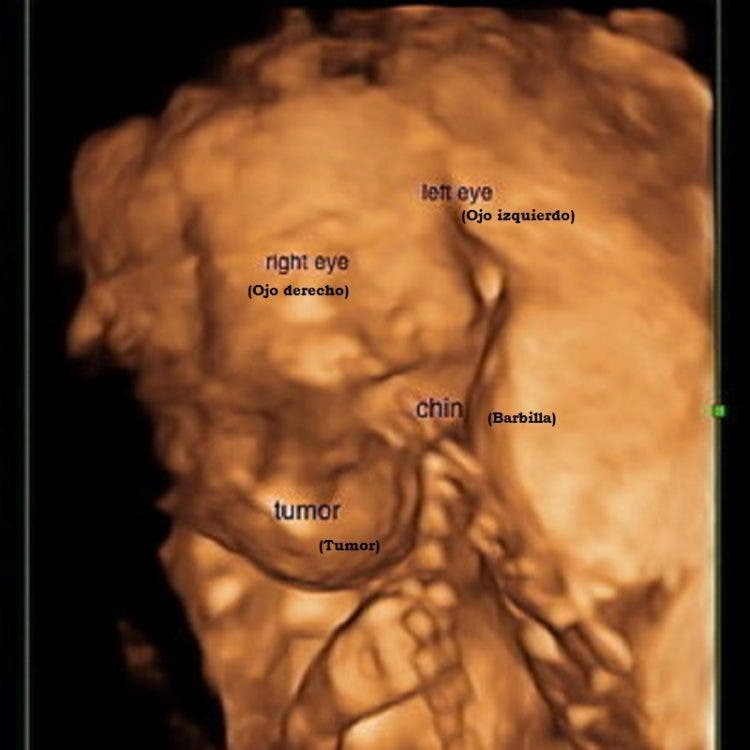

En febrero de 2016 Lindsey estaba embarazada de 18 semanas de su hija Omara y recibió un diagnóstico aterrador, los médicos hallaron un tumor en el cuello del bebé durante una ecografía de rutina.

Transcurrieron tres semanas y una resonancia magnética confirmó que el tumor se había triplicado de tamaño y crecía en su cabeza, pecho, pulmones y ojos y era inoperable.

Advertimos que las siguientes imágenes pueden herir sensibilidades.